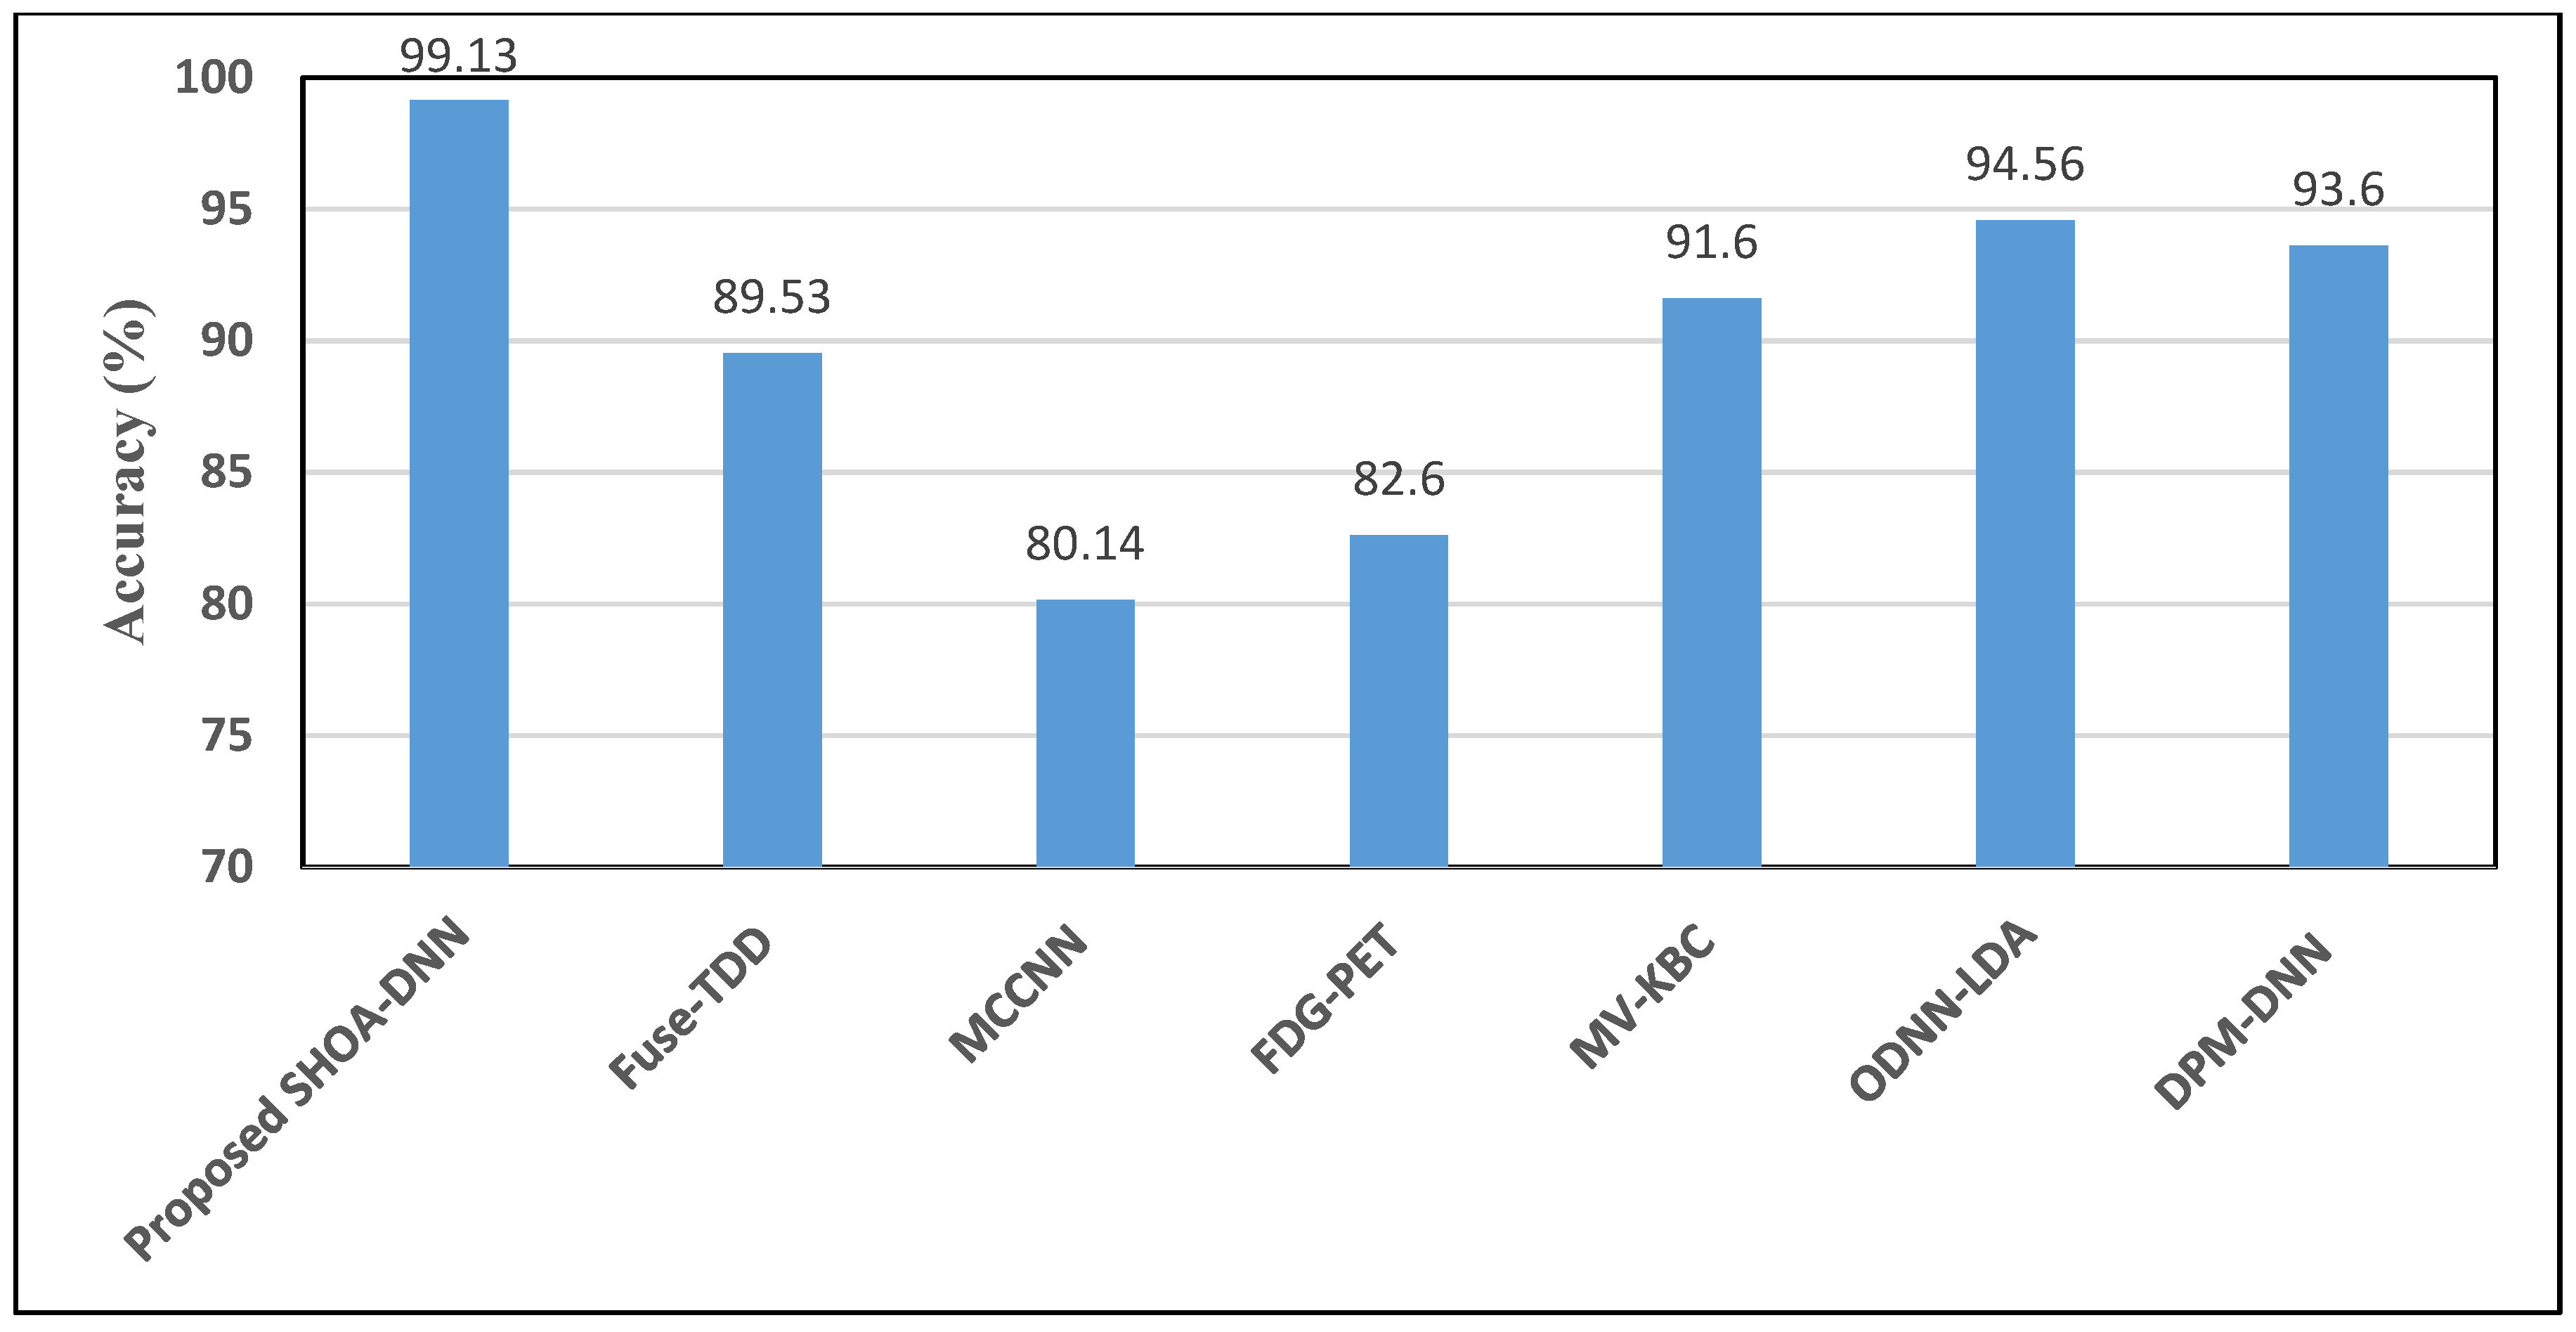

4.2. Performance Assessment of Proposed SHOA-DNN Model and Compared Benchmarked Schemes

| Compared Schemes | Accuracy | Precision | Recall | Specificity | F-Score |

|---|---|---|---|---|---|

| Proposed SHOA-DNN Model | 99.13 | 98.84 | 98.64 | 99.32 | 98.72 |

| Fuse-TDD [18] | 89.53 | - | 84.19 | 92.02 | 89.00 |

| MCCNN [20] | 80.14 | - | 77.00 | 93.00 | 87.00 |

| FDG-PET [22] | 82.60 | - | 92.10 | 53.40 | 82.00 |

| MV-KBC [23] | 91.60 | 87.75 | 86.52 | 94.00 | 87.13 |

| ODNN-LDA [24] | 94.56 | - | 96.2 | 94.2 | 95.12 |

| DPM-DNN [26] | 93.60 | - | - | - | - |